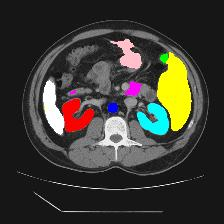

Medical image segmentation is one of the most fundamental tasks concerning medical information analysis. Various solutions have been proposed so far, including many deep learning-based techniques, such as U-Net, FC-DenseNet, etc. However, high-precision medical image segmentation remains a highly challenging task due to the existence of inherent magnification and distortion in medical images as well as the presence of lesions with similar density to normal tissues. In this paper, we propose TFCNs (Transformers for Fully Convolutional denseNets) to tackle the problem by introducing ResLinear-Transformer (RL-Transformer) and Convolutional Linear Attention Block (CLAB) to FC-DenseNet. TFCNs is not only able to utilize more latent information from the CT images for feature extraction, but also can capture and disseminate semantic features and filter non-semantic features more effectively through the CLAB module. Our experimental results show that TFCNs can achieve state-of-the-art performance with dice scores of 83.72\% on the Synapse dataset. In addition, we evaluate the robustness of TFCNs for lesion area effects on the COVID-19 public datasets. The Python code will be made publicly available on https://github.com/HUANGLIZI/TFCNs.

翻译:医学图像分解是医学信息分析的最根本任务之一,到目前为止已经提出了各种解决办法,包括许多深层次的学习技术,如U-Net、FC-DenseNet等。 然而,高精度医学图像分解由于医疗图像中存在固有的放大和扭曲,以及存在与正常组织密度相似的损伤,因此仍是一项极具挑战性的任务。在本文件中,我们建议TFCN(全面革命稠密网络的传输者)通过向FC-DenseNet引进ResLear-Transerferent(R-Transerfor)和Culvacial线性关注区(CLAB)来解决这一问题。TFCN不仅能够利用CT图像中更多的潜在信息来提取特征,而且还能够通过CLAB模块更有效地捕捉和传播语性特征和过滤非神经性特征。我们的实验结果表明,TFCN可以在Syapseion/SymblyDDS上以83CN-72 ⁇ 的分数实现状态。此外,我们在Synapse-DRIS数据设置上,我们还将评估CUTFTFI/LIS的可靠度。